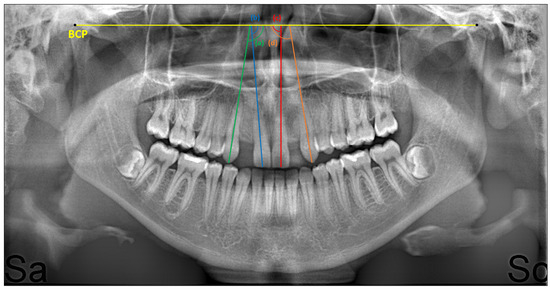

2. Materials and Methods